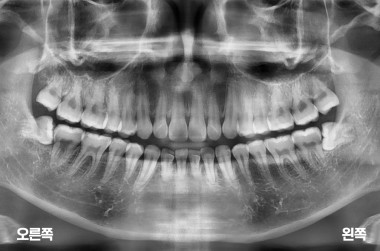

사랑니 4개 발치

MORE